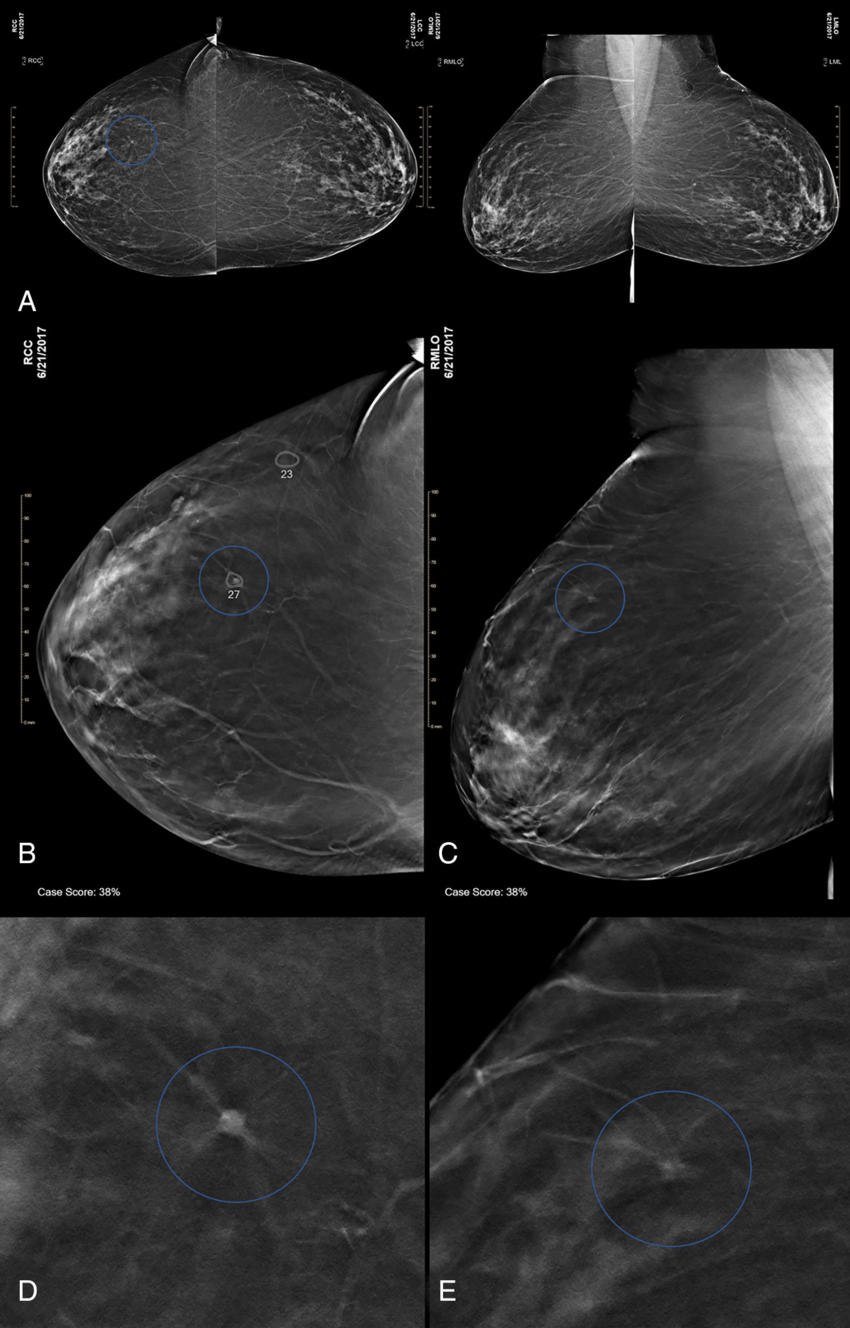

Figure 5. Images in a 47-yearold woman at screening with combination digital mammography (DM) and digital breast tomosynthesis (DBT).

High-res (TIF) version